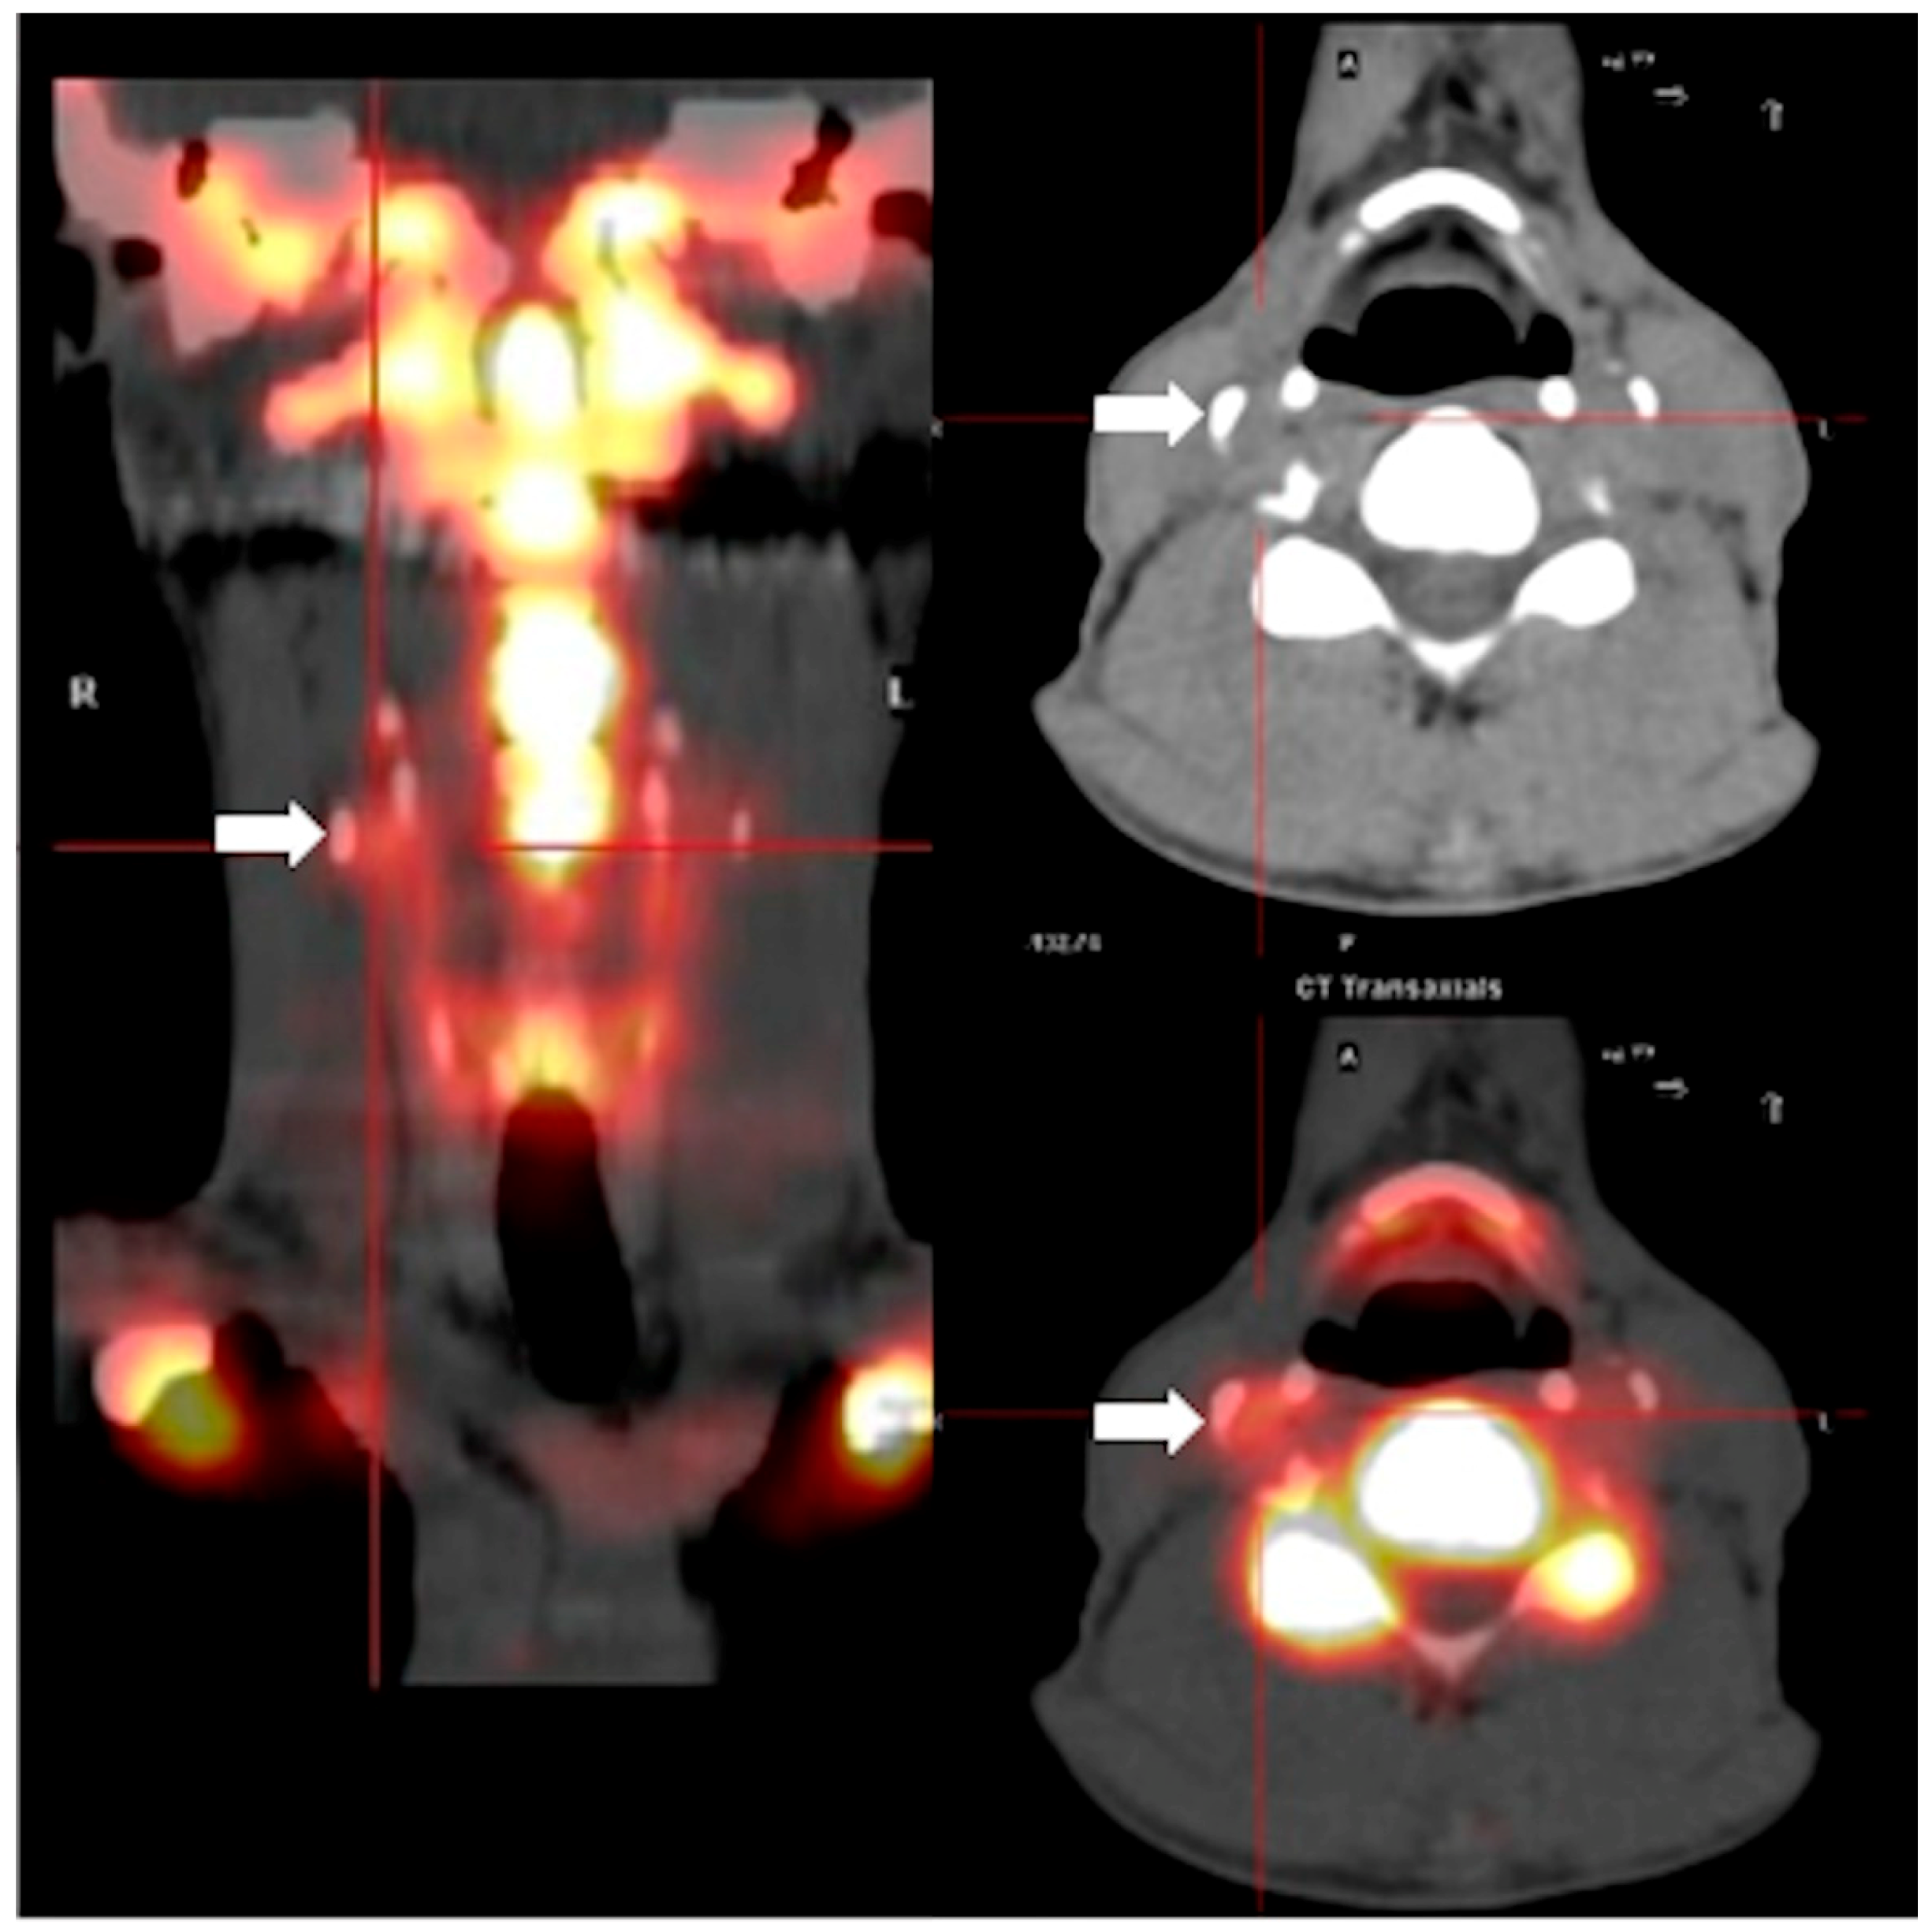

4.3.2. Positron Emission Tomography with 18F-Sodium-Fluoride

4.3.3. Image Analysis